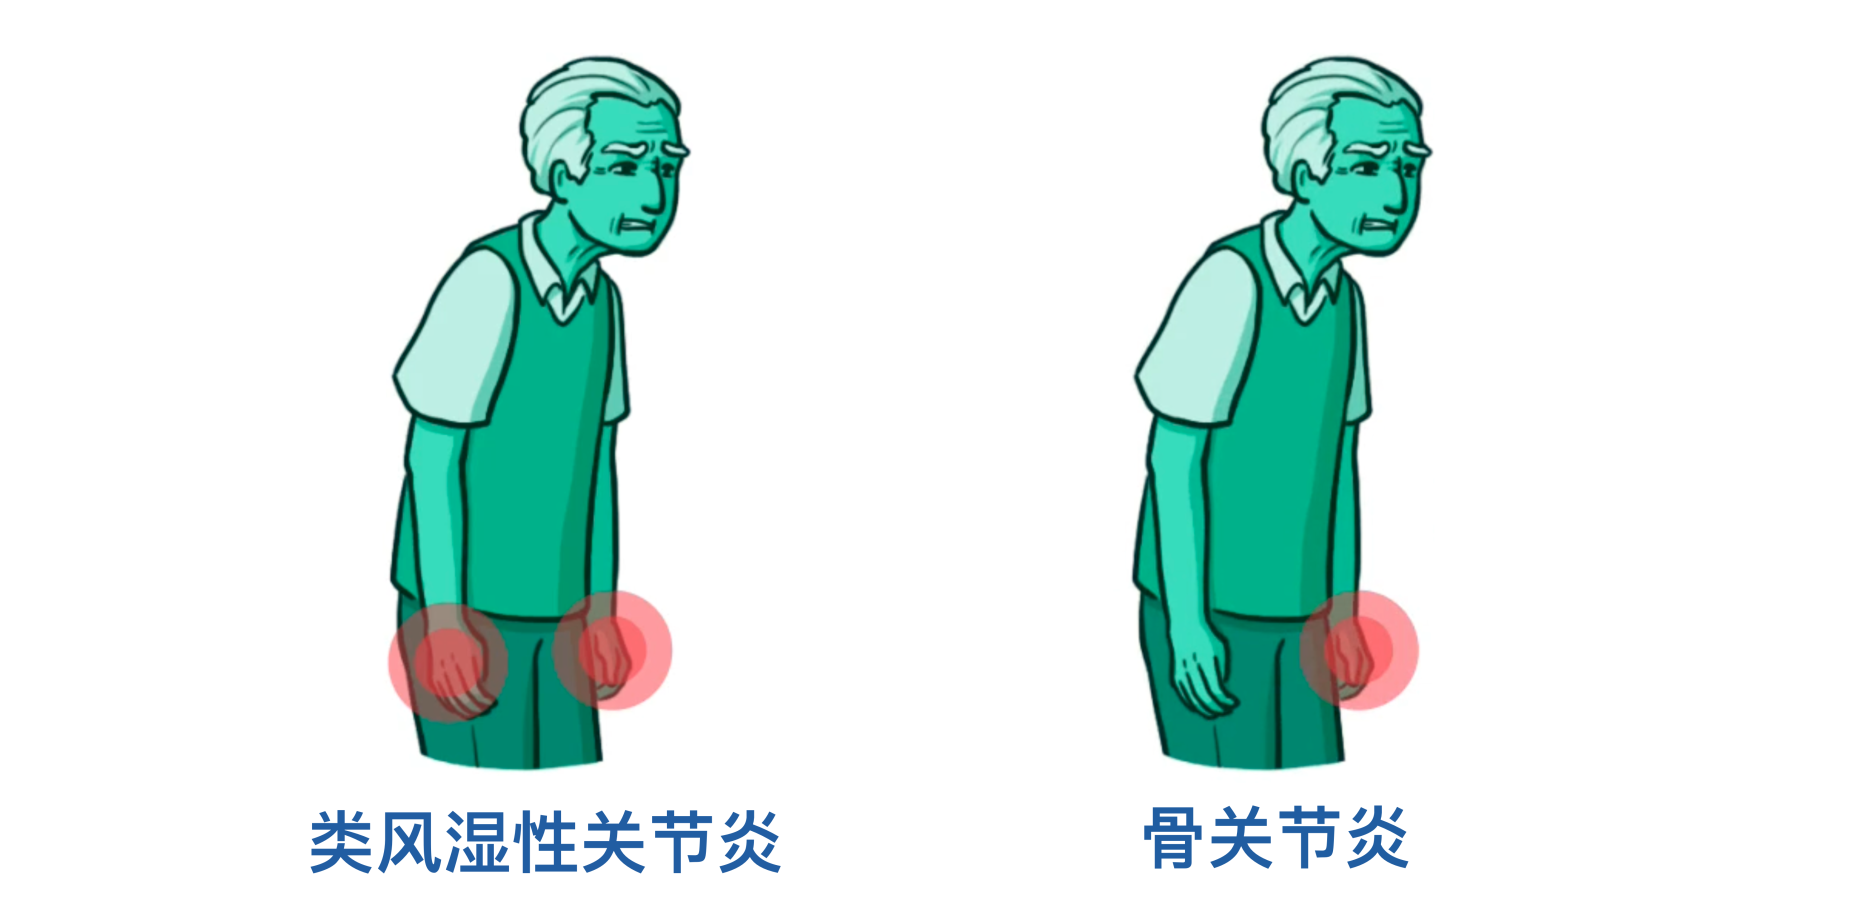

这里有一个临床要点:如果患者的晨僵持续超过30分钟,就需要考虑炎性关节炎,比如类风湿性关节炎。

另一个区分两者的方法是受累关节的分布模式。类风湿性关节炎往往呈对称性,也就是说身体两侧的关节会同时受累;而骨关节炎患者更可能表现为不对称的关节受累。